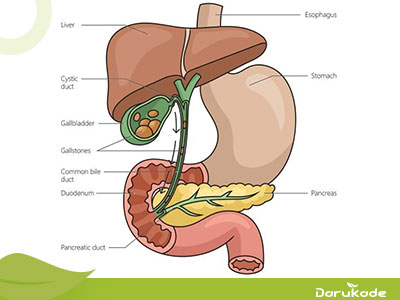

سنگ کیسه صفرا یکی از مشکلات شایعی است که بسیاری از افراد جامعه با آن دست و پنجه نرم میکنند. این سنگها میتوانند باعث ایجاد درد شدید در ناحیه شکم، تهوع و حتی مشکلات گوارشی شوند. یکی از روشهای غیرتهاجمی برای مدیریت سنگ کیسه صفرا، توجه به رژیم غذایی مناسب است. در این مقاله، به بررسی علل ایجاد سنگ کیسه صفرا، مواد غذایی مناسب برای دفع سنگ صفرا، مواد غذایی مضر برای سنگ صفرا و مکملهای گیاهی پیشنهادی میپردازیم.

سنگ کیسه صفرا زمانی تشکیل میشود که ترکیبات صفرا (مانند کلسترول، نمکهای صفراوی و بیلیروبین) به تعادل نمیرسند. عوامل زیر میتوانند در تشکیل این سنگها نقش داشته باشند:

افزایش کلسترول صفرا یکی از علل ایجاد سنگ سفرا است. سطح بالای کلسترول میتواند منجر به تشکیل سنگهای کلسترولی شود. یکی از دلایل اصلی این مسئله معمولاً استفاده زیاد از غذاهای پرچرب و کم تحرکی است.

از علل دیگر ایجاد سنگهای صفراوی میتوان به کاهش تخلیه کیسه صفرا اشاره کرد. اگر کیسه صفرا به طور کامل تخلیه نشود، ممکن است مواد جامد در آن تهنشین شده و سنگ تشکیل دهند. این مشکل اغلب در افرادی که غذای پرچرب مصرف میکنند یا ناشتاییهای طولانی مدت و غیر اصولی را تجربه میکنند، رخ میدهد.